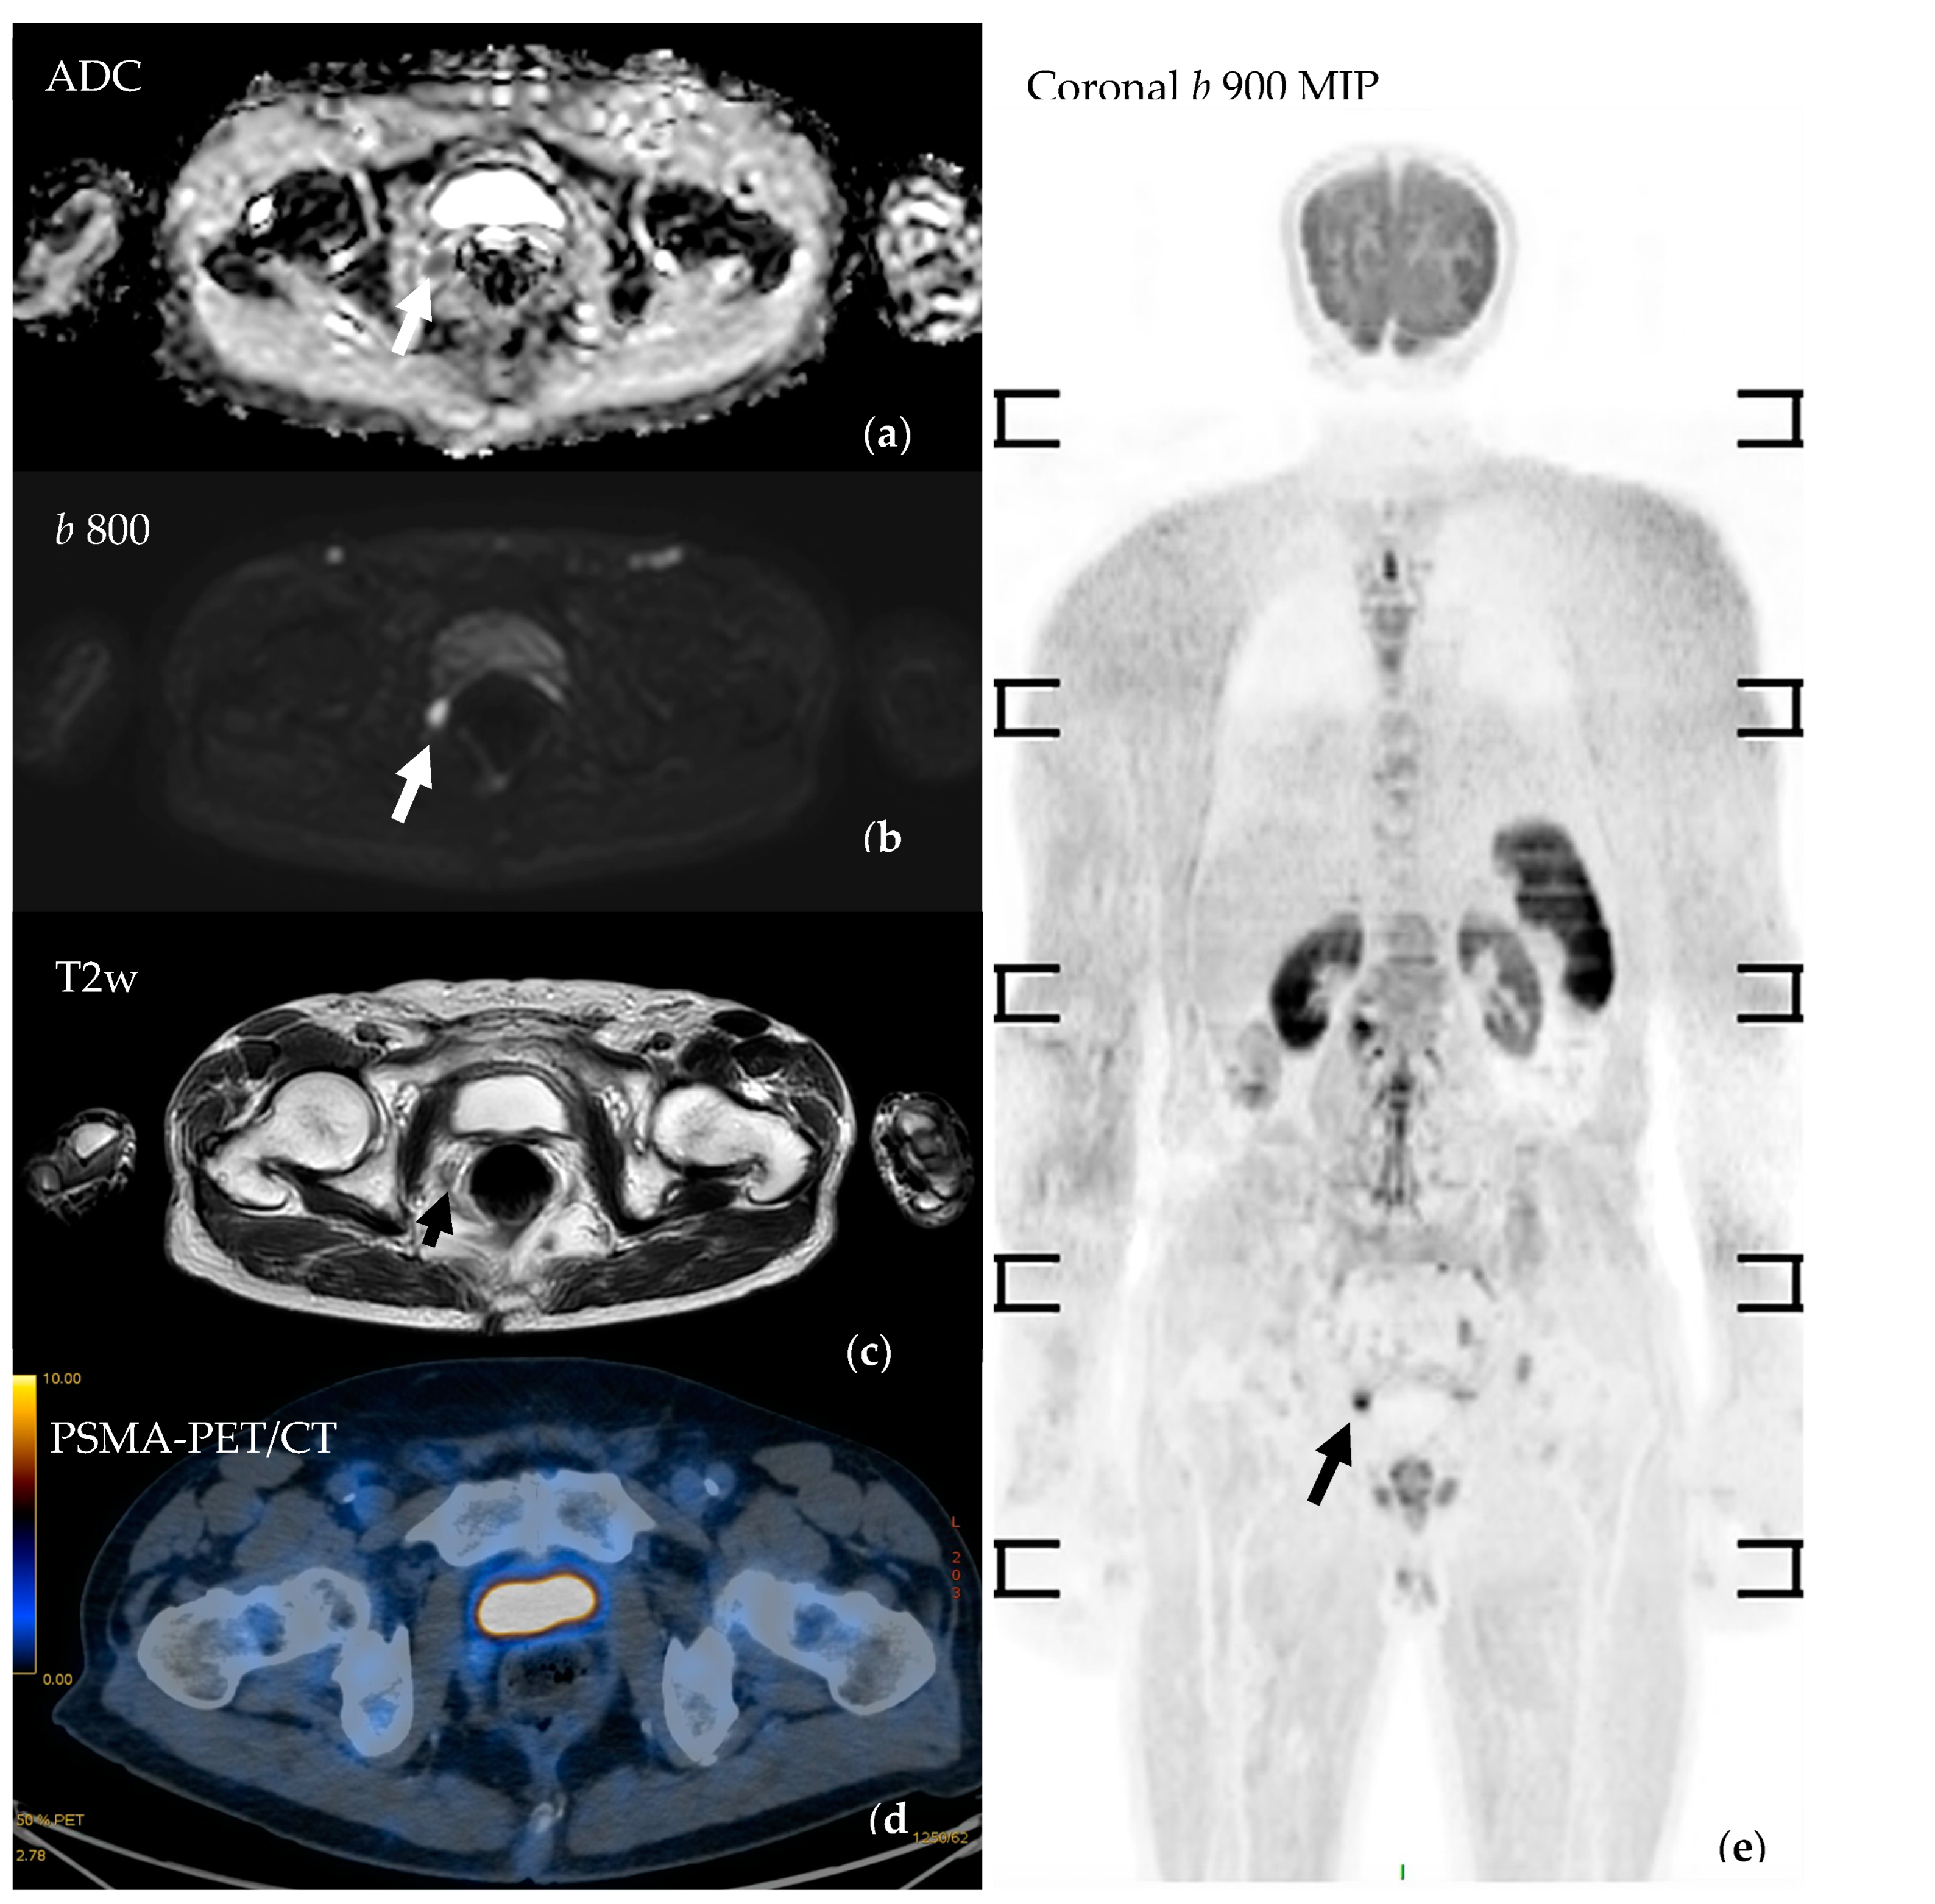

3.4.4. Assessing Local Disease and Biochemical Recurrence

- Van Damme, J.; Tombal, B.; Collette, L.; Van Nieuwenhove, S.; Pasoglou, V.; Gérard, T.; Jamar, F.; Lhommel, R.; Lecouvet, F.E. Comparison of Ga-Prostate Specific Membrane Antigen (PSMA) Positron Emission Tomography Computed Tomography (PET-CT) and Whole-Body Magnetic Resonance Imaging (WB-MRI) with Diffusion Sequences (DWI) in the Staging of Advanced Prostate Cancer. Cancers 2021, 13, 5286. [Google Scholar] [CrossRef] [PubMed]